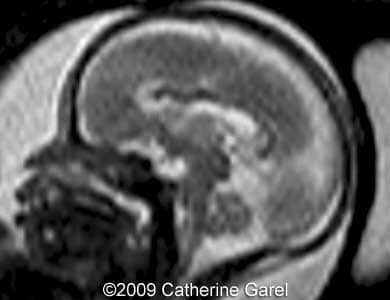

Images 7,8: MRI Image 7 shows a wavy midline structure which was detected on the ultrasound images (Images 4,6), the structure is hypodense on the MRI images. Image 8 shows an interhemispheric fissure in the anterior and posterior region.

Case262_7

Case262_8